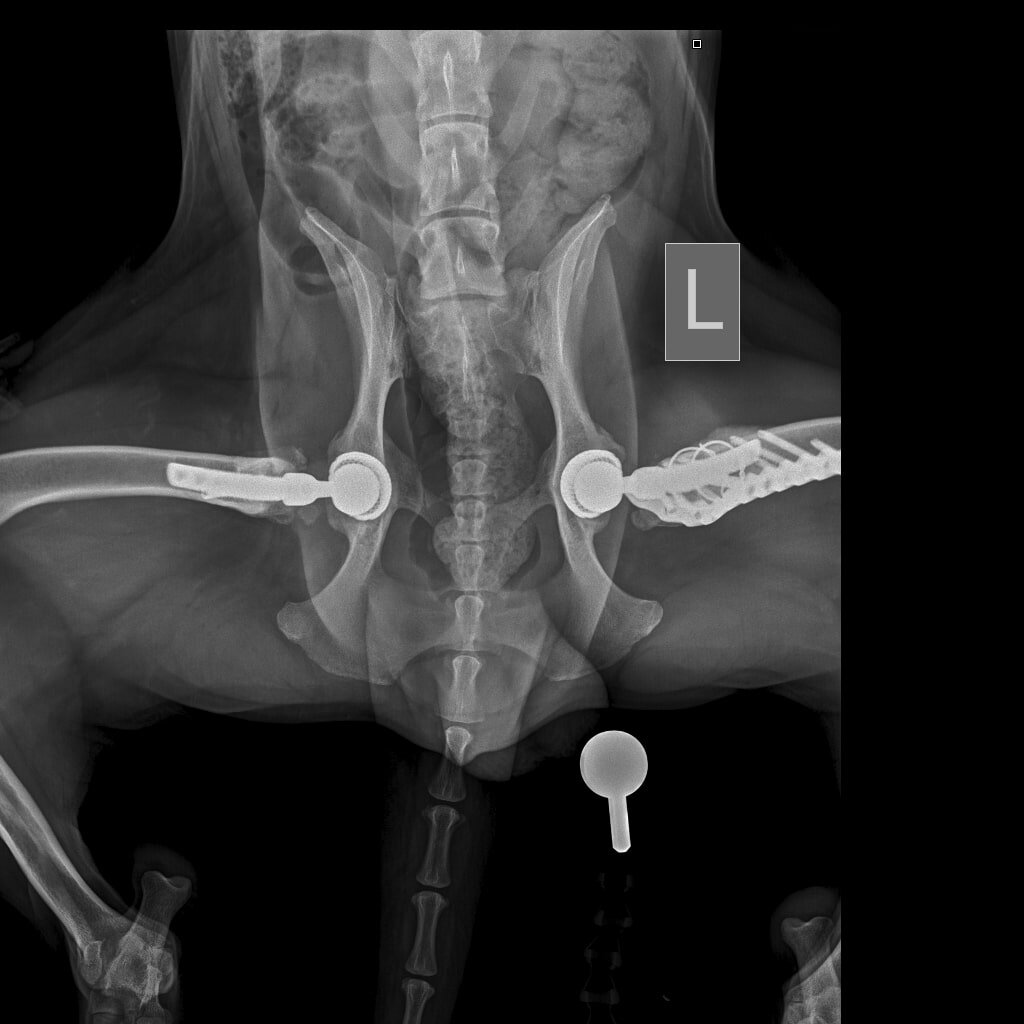

Итак, у ризеншнауцера Бруно из Луганской области состоялась вторая операция по замене тазобедренного сустава, теперь уже на левой лапе. Сама операция пошла с осложнением и длилась три с половиной часа вместо обычных полутора-двух. Первое, что сказал оперирующий врач, что ещё 4-6 месяцев, и шейка бедра бы просто сломалась, так что успели очень вовремя. Но самая большая проблема оказалась не в этом, а в том, что за счёт длительного воспалительного процесса существенно изменилась структура самой кости бедра, причём настолько, что если пришлось бы судить по картине сустава и кости, собаке должно было быть лет десять, а не четыре.

И в добавок ко всему канал бедренной кости, в которую должна была встать ножка протеза, практически зарос тканями (туда должна быть вставлена ножка протеза ), а мышцы за длительное время работы на полусогнутой конечности сократились, образовали контрактуры (стянулись, не давая двигаться лапе как положено), и вывернуть кость в удобное положение никак не получалос

И в добавок ко всему канал бедренной кости, в которую должна была встать ножка протеза, практически зарос тканями (туда должна быть вставлена ножка протеза ), а мышцы за длительное время работы на полусогнутой конечности сократились, образовали контрактуры (стянулись, не давая двигаться лапе как положено), и вывернуть кость в удобное положение никак не получалось.

Всё это уже было заметно и на снимках, сделанных уже когда собака была под наркозом перед самой операцией - прооперированная правая нога свободно вытянулась, а левая, которую ещё не "резали", даже при полном расслаблении мышц не смогла принять ту же позицию. А ещё мышц уже на прооперированной правой ноге больше, чем на непрооперированной левой, т.е. Бруно уже старался переносить основную нагрузку на прооперированную ногу. В конце-концов канал бедренной кости был расчищен, но при установке и закреплении ножки протеза образовалась продольная трещина кости. Поэтому кость пришлось дополнительно укреплять проволокой, чтоб трещина не пошла дальше, плюс дополнительно поставили пластину. Все этапы операции контролировались сразу на столе операционным рентгеном, после операции был сделан еще ряд снимков, уже на стационарном рентгене.